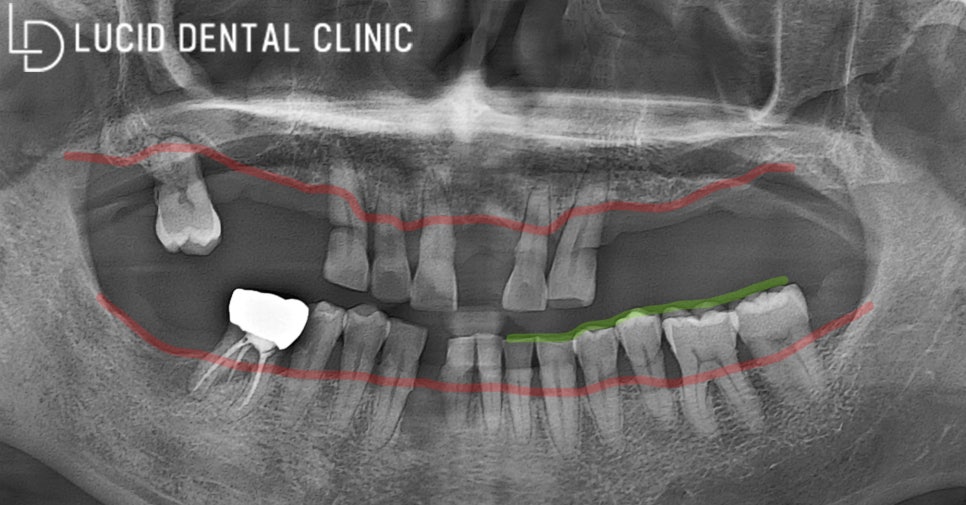

지금 보실 건 파노라마 방사선 사진인데요.

파노라마 사진으로 전체 구강과 함께

염증 감염 여부까지 파악할 수 있어

구강 검진 때 필수로 진행하고 있습니다.

사진을 보자마자 군데군데

비어있는 곳이 많이 보이고 있는데요.

발거하고 제때 처치 받지 않아

대합치에 정출이 발생했습니다.

그뿐만 아니라

비어있는 곳을 향하여

치아 이동이 진행되었는데요.

치조골이 꽤 소실되었고,

충치까지 발생하였기 때문에

빠른 조치가 필요했습니다.